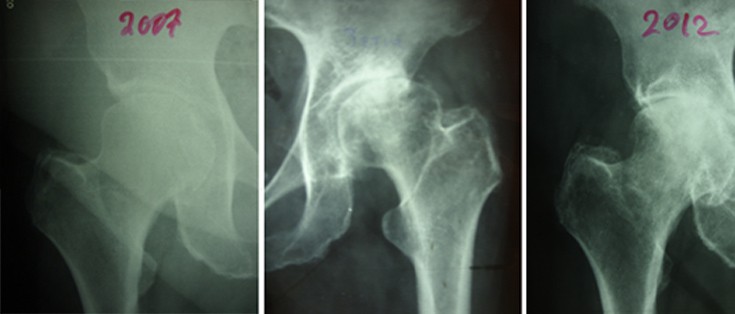

Η οστεοαρθρίτις του ισχίου είναι η κατάληξη όλων των παθήσεων που έχουν ήδη αναφερθεί, δηλ. του συγγενούς εξαρθρήματος, της δυσπλασίας, του CAM, της επιφυσιολίσθησης, του Perthes, της φλεγμονής, του υποκεφαλικού κατάγματος (που διαταράσσει την κυκλοφορία αίματος της κεφαλής), του κατάγματος της κοτύλης, του εξαρθρήματος του ισχίου.